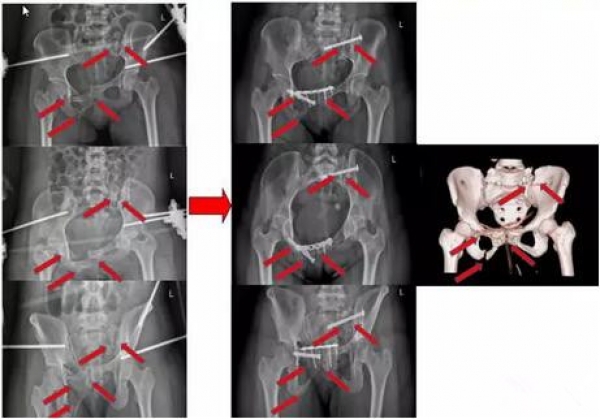

术后CT影像(2017.10.05)

术后治疗和随访

术后给予抗生素消炎、利伐沙班预防血栓、氟比洛芬酯和口服镇痛药物、营养支持等对症治疗;

复查影像资料结果回报后,嘱患者适当功能锻炼,可于病床上早期翻身、坐起等,两周拆线后出院;

门诊定期复查,患者为骨盆环单侧损伤,术后六周在助行器辅助下下地行走锻炼,本例骨盆髋臼的微创手术以极小手术创伤,获得了优良的治疗效果!